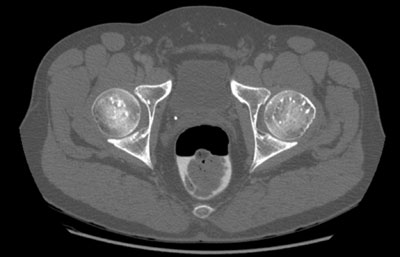

Radiologie Quiz 43

Im Rahmen einer Prostataabklärung wird bei einem 51-jährigen Mann eine Computertomographie des kleinen Beckens durchgeführt.

Knochenbeschwerden werden verneint. Hier ein CT-Schnitt im Bereich der Femurköpfe: